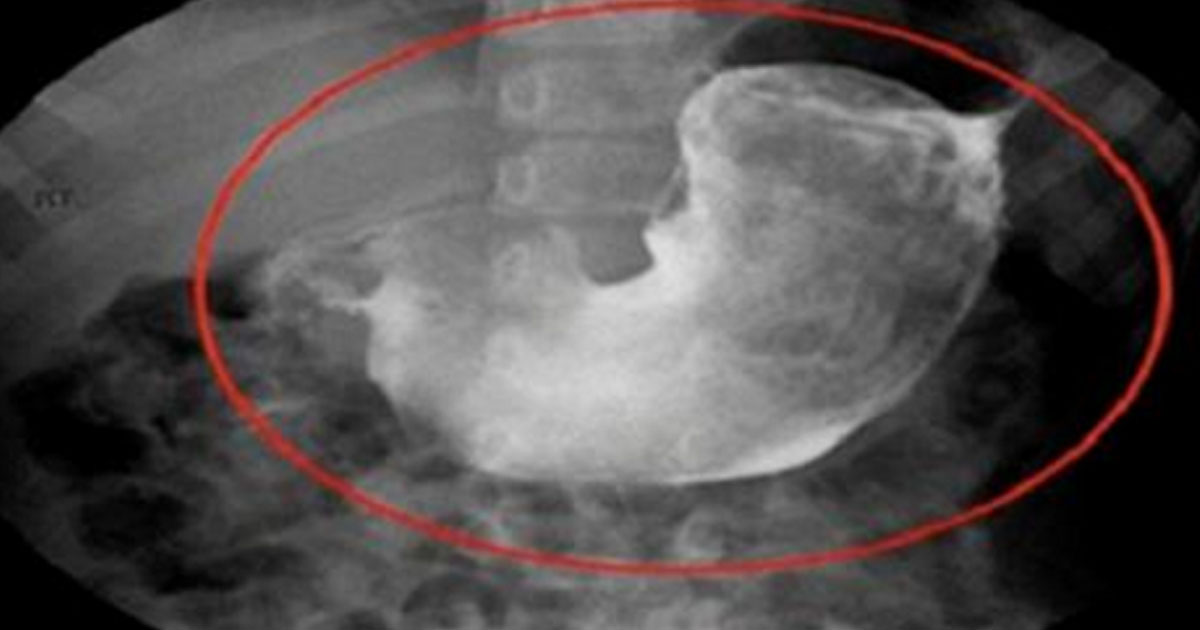

Подозревая, что у Бэрроу, скорее всего, рак яичnиков, гинеколог начала обследовать ее vлагалище. И именно того специалист обнаружила какие-то странные волоски внутри организма пациентки.

Женщина-доктор изначально подумала, что это волоски остались после использования противоzачаточного средства, которое вставляется в mатку. Удалив эти волоски, доктор показала комок Бэрроу – это был настоящий ‘’меховой шар’’!

‘’ЧЕРТ ПОБЕРИ!!! ВЫ МОЖЕТЕ В ЭТО ПОВЕРИТЬ? ВНУТРИ МОЕГО VЛАГАЛИЩА БЫЛО ОБНАРУЖЕНО ПОЧТИ 2 ДЮЙМА КОШАЧЬЕЙ ШЕРСТИ, СВЕРНУТОЙ В КЛУБОК. ВОТ ОНА – ПРИЧИНА МОЕГО ДИСКОМФОРТА. БОЖЕЕЕЕЕЕЕЕЕЕЕЕЕЕЕЕЕЕЕЕЕЕЕЕЕЕЕЕЕЕЕЕЕЕЕЕЕЕЕЕЕЕЕ!» Вот, как отреагировала Бэрроу после похода к гинекологу.